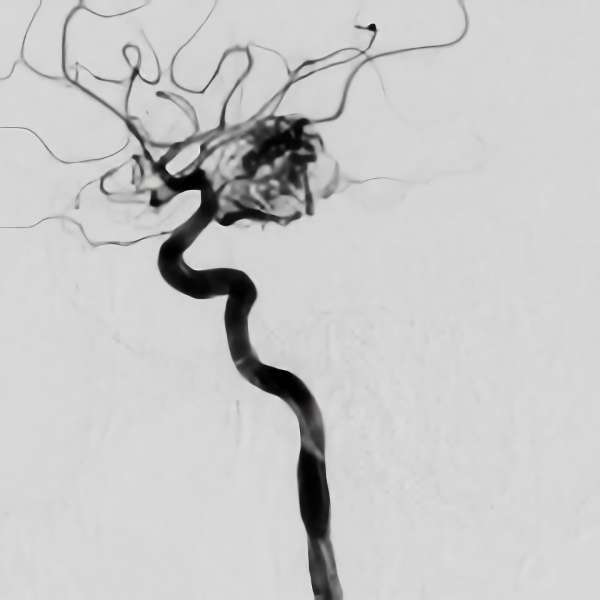

脳血管撮影

手術前

手術後